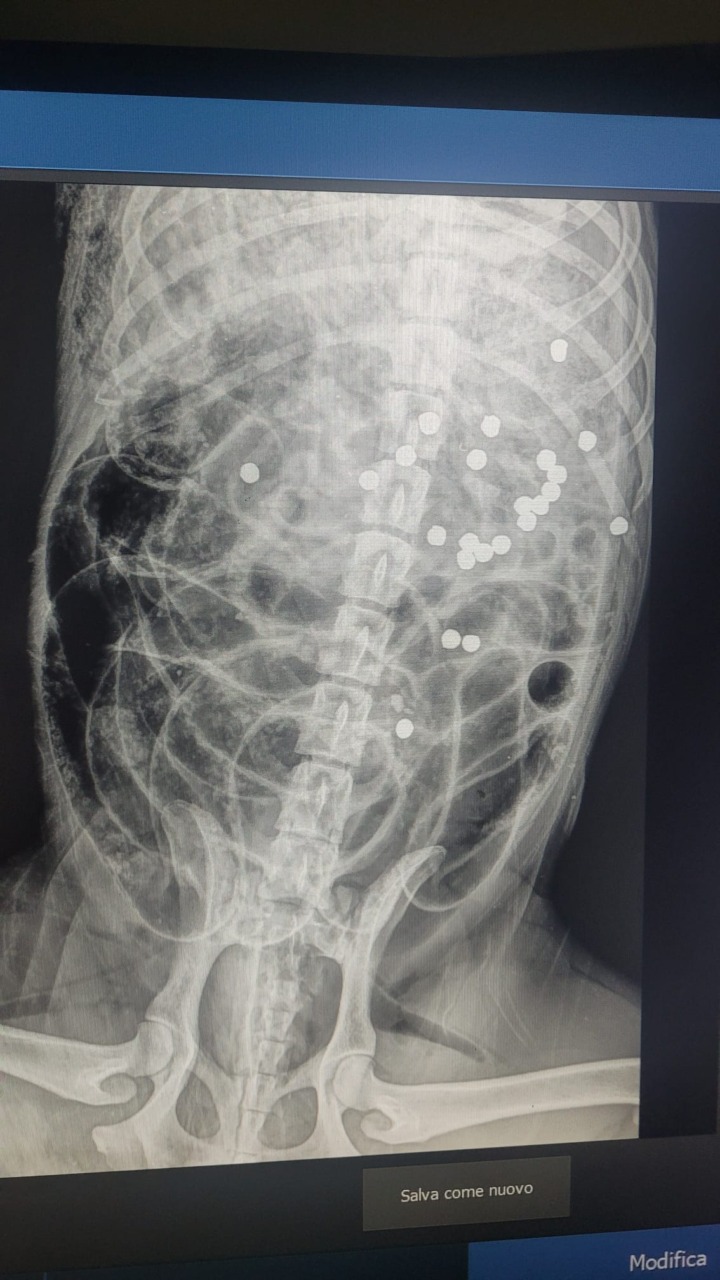

Sulla tragica vicenda che vede protagonista un cane ucciso con un colpo di fucile da caccia con 24 pallini, il 14 novembre scorso alle  3.00 di notte,  di razza Labrador e rinvenuto dal proprietario la mattina alle 07.30, in una pozza di sangue sul ponte del fiume Selicella sulla Migliara 49, sono riusciti  a risalire all’orario dello sparo in quanto  è stato udito da un abitante della zona. Ad  intervenire è l’Associazione difesa diritti animali A.D.D.A.” Quasi sicuramente è stato qualcuno che passava in automobile, che si è fermato od addirittura abbia sparato dal suo interno, – scrive in una nota – non si capisce quale possa essere stato il motivo che ha spinto una persona ad uccidere senza pietà un animale indifeso che non poteva aver dato alcun fastidio, essendo di notte in aperta campagna, ma non si tratta solo dell’uccisione dell’animale, già di per se un fatto gravissimo condannabile dalla legge per il reato cui all’art. 544-ter del codice penale, ma è altrettanto gravissimo che ci sia una persona che vaga nottetempo con un arma carica, in una giornata in cui la caccia per altro è vietata”.